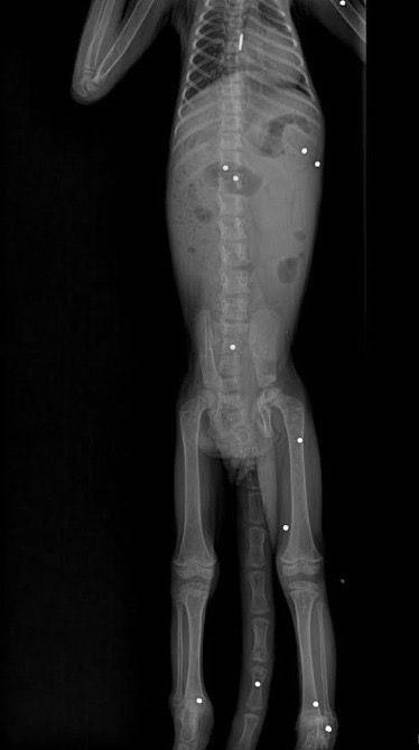

Después de que se le realizara una revisión médica atenta y los estudios radiográficos correspondientes, fue posible saber que el animal presentaba grandes afectaciones en su sistema osteomuscular. Dichas radiografías permitieron evidenciar que el mono tenía 19 perdigones alojados en diferentes partes del cuerpo; de ahí la magnitud del daño en su salud.

Los proyectiles, de aproximadamente 3 milímetros de diámetro cada uno, estaban distribuidos en varias zonas y afectaron directamente la movilidad del animal, especialmente en una de sus extremidades, lo cual hizo que su salud se deteriorara de manera progresiva hasta causar su muerte.

“Al realizar las ayudas diagnósticas pertinentes, particularmente el examen radiográfico, se evidenció la presencia de 19 perdigones alojados en el cuerpo del individuo”, dijo Andrés Rodríguez, médico veterinario.